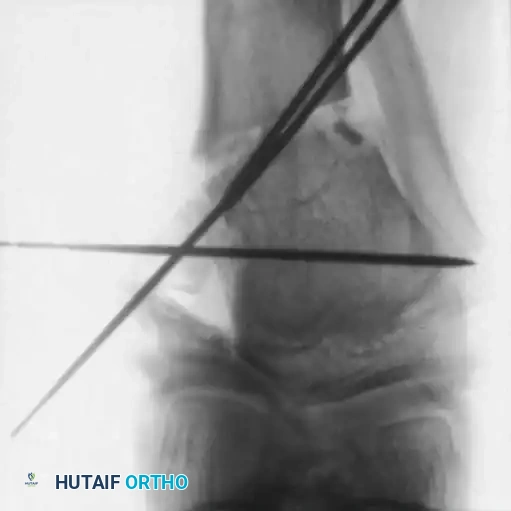

1. Intraepiphyseal Osteotomy: To elevate the depressed medial tibial plateau and reconstruct the horizontal joint line.

2. Metaphyseal Valgus Osteotomy: To correct the diaphyseal varus angulation.

Schoenecker et al. reported successful elevation of the medial tibial plateau in patients aged 10 to 13 years with average preoperative varus deformities of 25 degrees. The procedure involves an osteotomy through the epiphysis, elevating the medial plateau to match the lateral plateau, and supporting the elevation with structural bone graft.

Surgical Warning: Intraepiphyseal osteotomies carry a high risk of intra-articular fracture, avascular necrosis of the elevated fragment, and permanent physeal arrest. Meticulous fluoroscopic guidance and rigid fixation are absolute requirements.